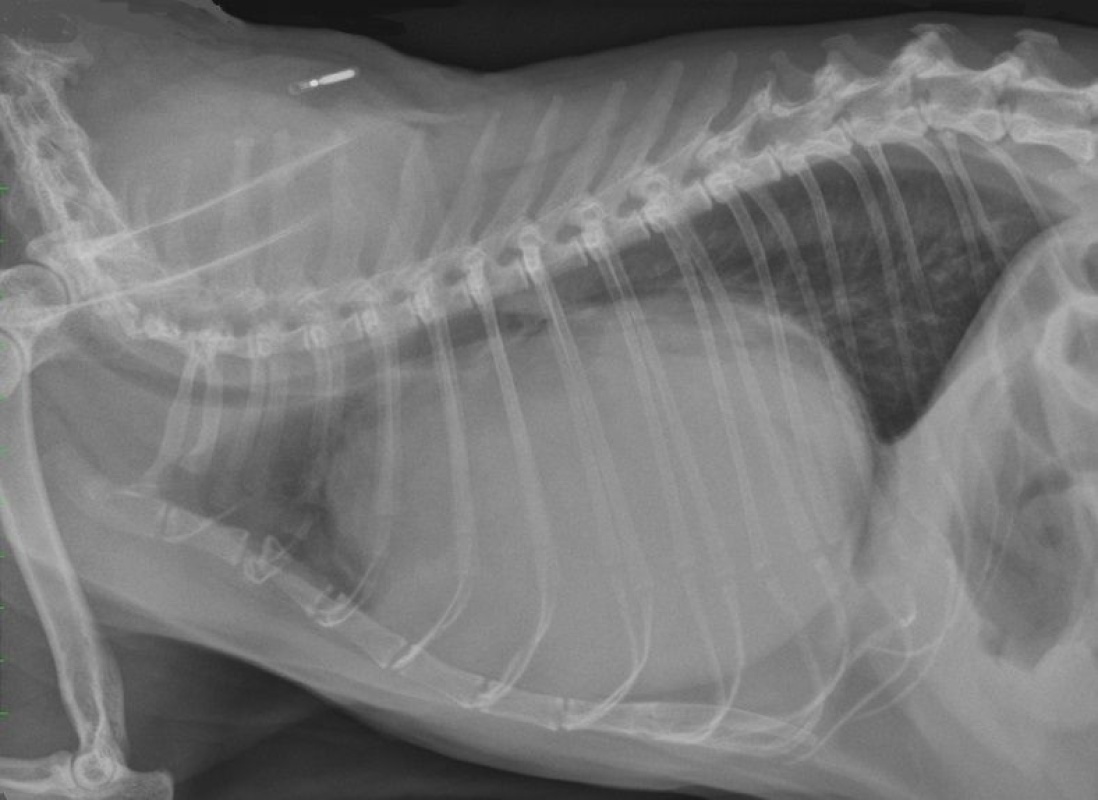

From www.dreamstime.com

Cat X Ray. Diaphragmatic Hernia in Cat. Stock Image Image of anatomy Can A Cat Live With A Diaphragmatic Hernia learn about the causes, signs, diagnosis, and treatment of diaphragmatic hernia in cats, a condition that affects the muscle separating. A hernia occurs when there's an abnormal hole in the muscle wall of the abdomen or diaphragm. diaphragmatic hernia in cats is a condition that happens when a tear in the diaphragm allows organs situated below the. Diaphragmatic. Can A Cat Live With A Diaphragmatic Hernia.